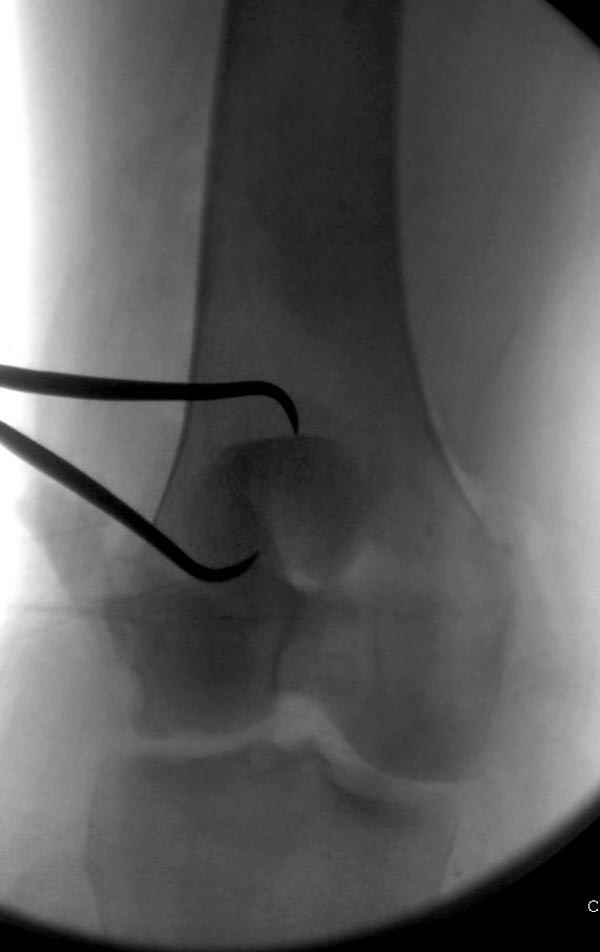

В приемное отделение поступает больная 22 лет, во время аварии ремень безопасности не был пристегнут, в крови большое количество кокаина.В приемном срочная интубация и седация, сделаны снимки.Диагностирован: открытый вывих левого коленного сустава.

Заключительный диагноз: Открытый вывих коленного сустава, перелом надколенника, разрыв собственной связки надколенника

На операции: Irrigation&Debridment около 10 литров раствора, по два стержня в сегменте, фиксация диагонального, с дефектом, перелома надколенника тремя cannulated 4мм шурупами, ушивание поперечного разрыва связки 5.0 Ethibon sutures, разрыв находился на 2 см ниже надколенника (срез чем-то острым), повторная ирригация раны, взятие посева на аэробическую и анэробическую культуру, окончательная фиксация стержней наружного фиксатора 50см Carbon Fiber Bars, вакуумное закрытие. Мониторинг показал, что компартмент синдрома нет.

Сегодня досылаю остальные снимки, которые не прошли вчера. Как вчера писал, после фиксации перелома надколенника с дефектом кости и собственной связки, наложили ваккуум и наружный фиксатор. (снимки 4-9)